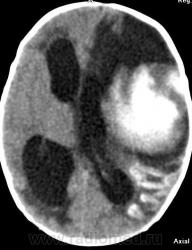

Я думаю, это больше похоже на кровоизлияние - неоднородная структура с гиперденсным компонентом. Плюс ко всему - клиника, судя по всему, с острым началом. Опухоли быстро не растут.

Смущает то, что кровоизлияние как бы в капсуле. А что с извилинами? Пропитывание кровью?

Паразитарная киста - это эхинококк? Образование имеет плотность свежей крови, так что кровоизлияние не вызывает сомнений. Но вот возможно кровоизлияние в опухоль или в результате какой-либо сосудистой патологии, например, ангиоматоза Штурге-Вебера. Насчет течения родов попробую уточнить.

Светлые участки 70 ед Н - плотности крови.

А ведь кровоизлияние есть субарохноидально.

Денди Уокер? Не думаю, хотя надо посмотреть аксиалы ниже уровня намёта. А пока явно вижу признаки Sturge-Weber syndrome - encephalotrigeminal angiomatosis синдром со всеми вытекающими.